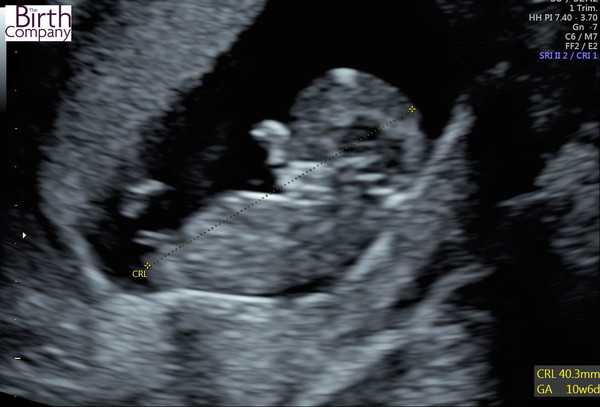

I also had my first scan this Sunday as my DH and I decided to get an NIPT test done due to my age, and the scan was included. It was so lovely to see the baby literally dancing around in there, and found out I am a few days further along than I thought, so 11weeks. Now I'm just waiting on the results of the NIPT (fingers crossed for a good result) and excited about my Dating Scan, which will actually happen closer to 14w if the first scan was accurate.

Sharing a little photo from my scan, I keep looking at it and smiling!

Aw @WolfMother326 what a lovely post! 🥰 gorgeous photo, almost looks like we’re getting a wave! ❤️

Thanks @Thisisbananas3, I agree, looked like a little wave :)